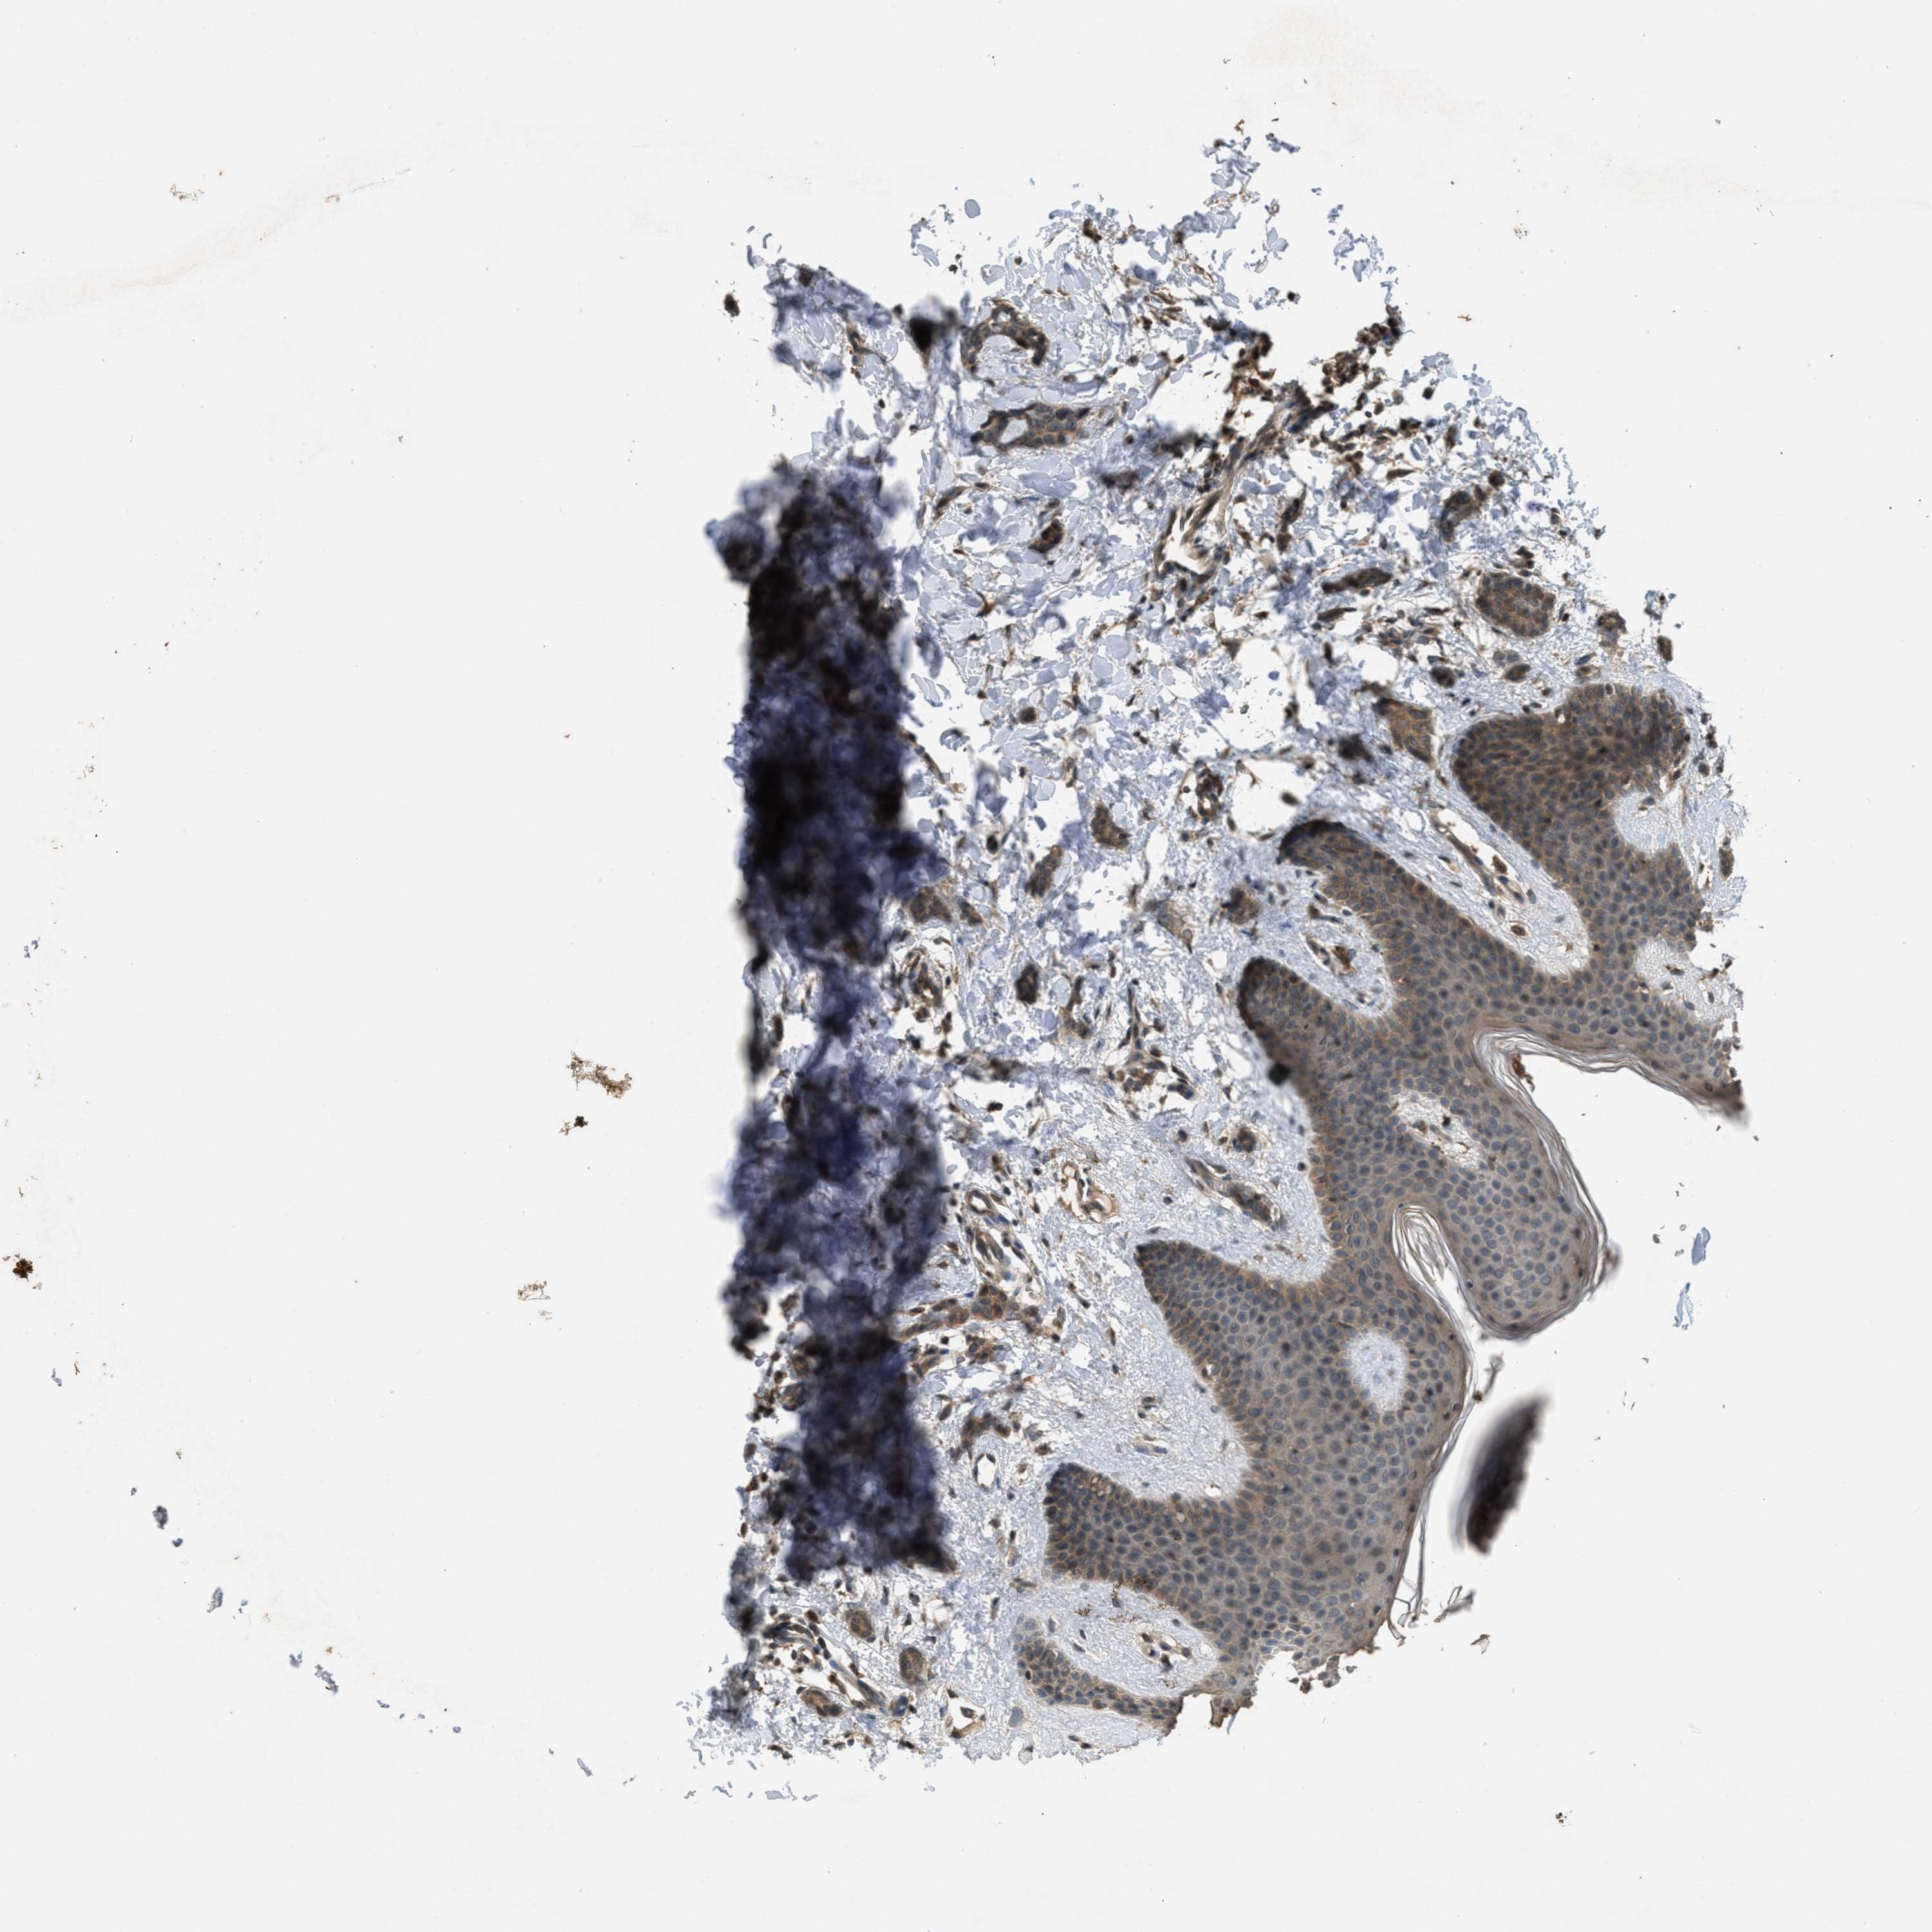

CANCER BREAST CANCER Show tissue menu

BRCA TCGA BRCA VALIDATION PROTEIN EXPRESSION

ANTIBODIES

AND

VALIDATION